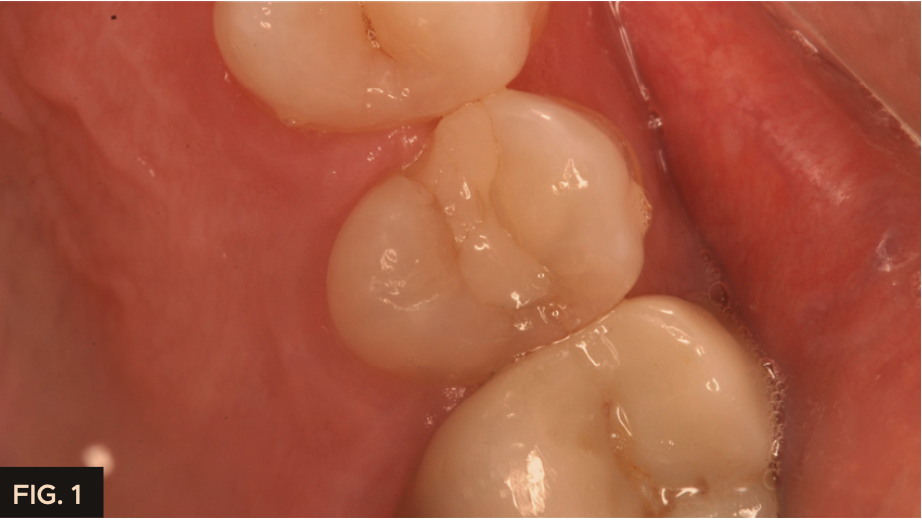

A 55-year-old patient presented to my office with tooth pain upon biting from his second bicuspid. Upon further examination a crack was noted on the mesial marginal ridge. (FIG. 1)